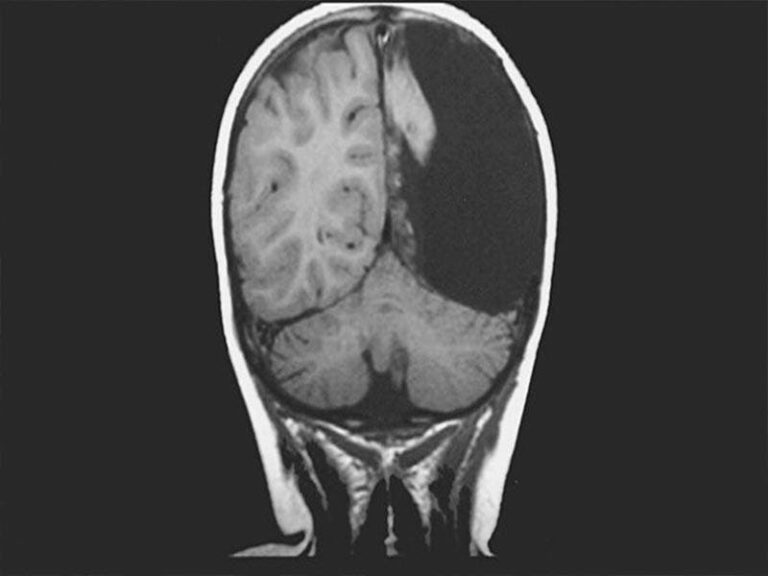

Hombre vive solo con la mitad de su cerebro.- Médicos en Rusia descubrieron a través de una tomografía de la cabeza de ex soldado; que el hombre ha vivido más de 60 años solo con la mitad de su cerebro.

El exsoldado ingresó al hospital debido a que tenía trastornos circulatorios, sin embargo después de un análisis los especialistas se dieron cuenta que el hombre tenía un “agujero negro”  en su hemisferio izquierdo.

Los médicos se sorprendieron al ver que la mitad del cerebro del paciente tenía un agujero negro, sin embargo el exsoldado nunca tuvo problemas motores ni visuales por lo que siempre llevó una vida normal sin la mitad de su cerebro.

Los médicos indicaron que el caso del exsoldado es único, debido a que se trata de una falla congénita, por lo que ahora “si un hemisferio está dañado o no desarrollado, el segundo asume completamente las funciones de ambos”.